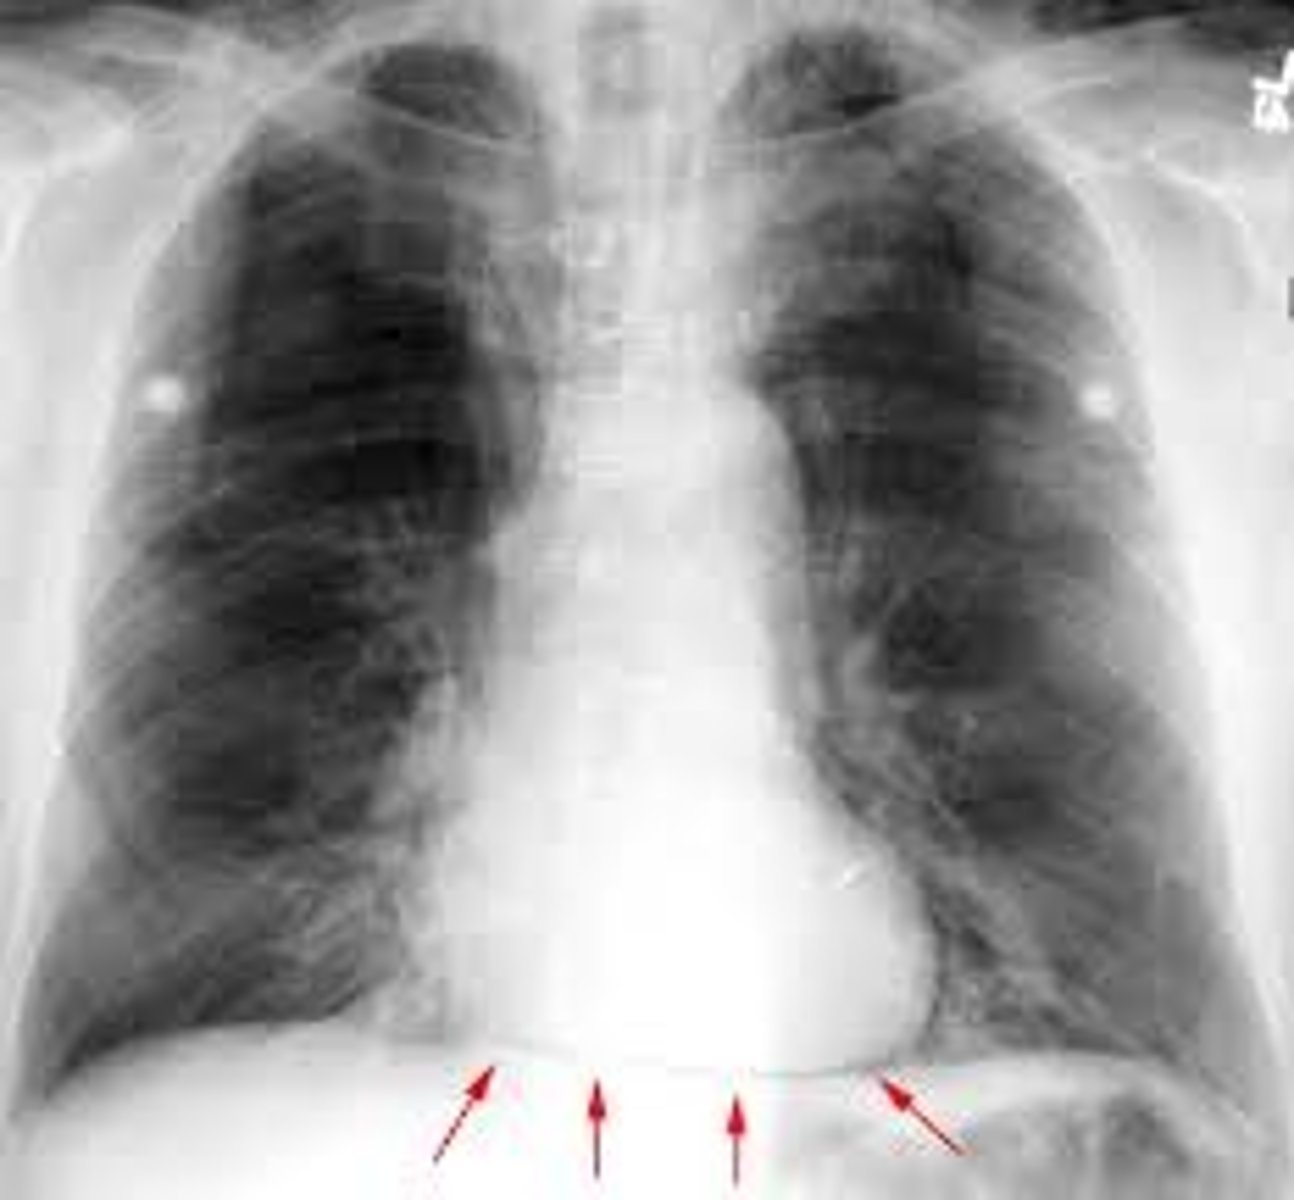

Inferior border of the heart